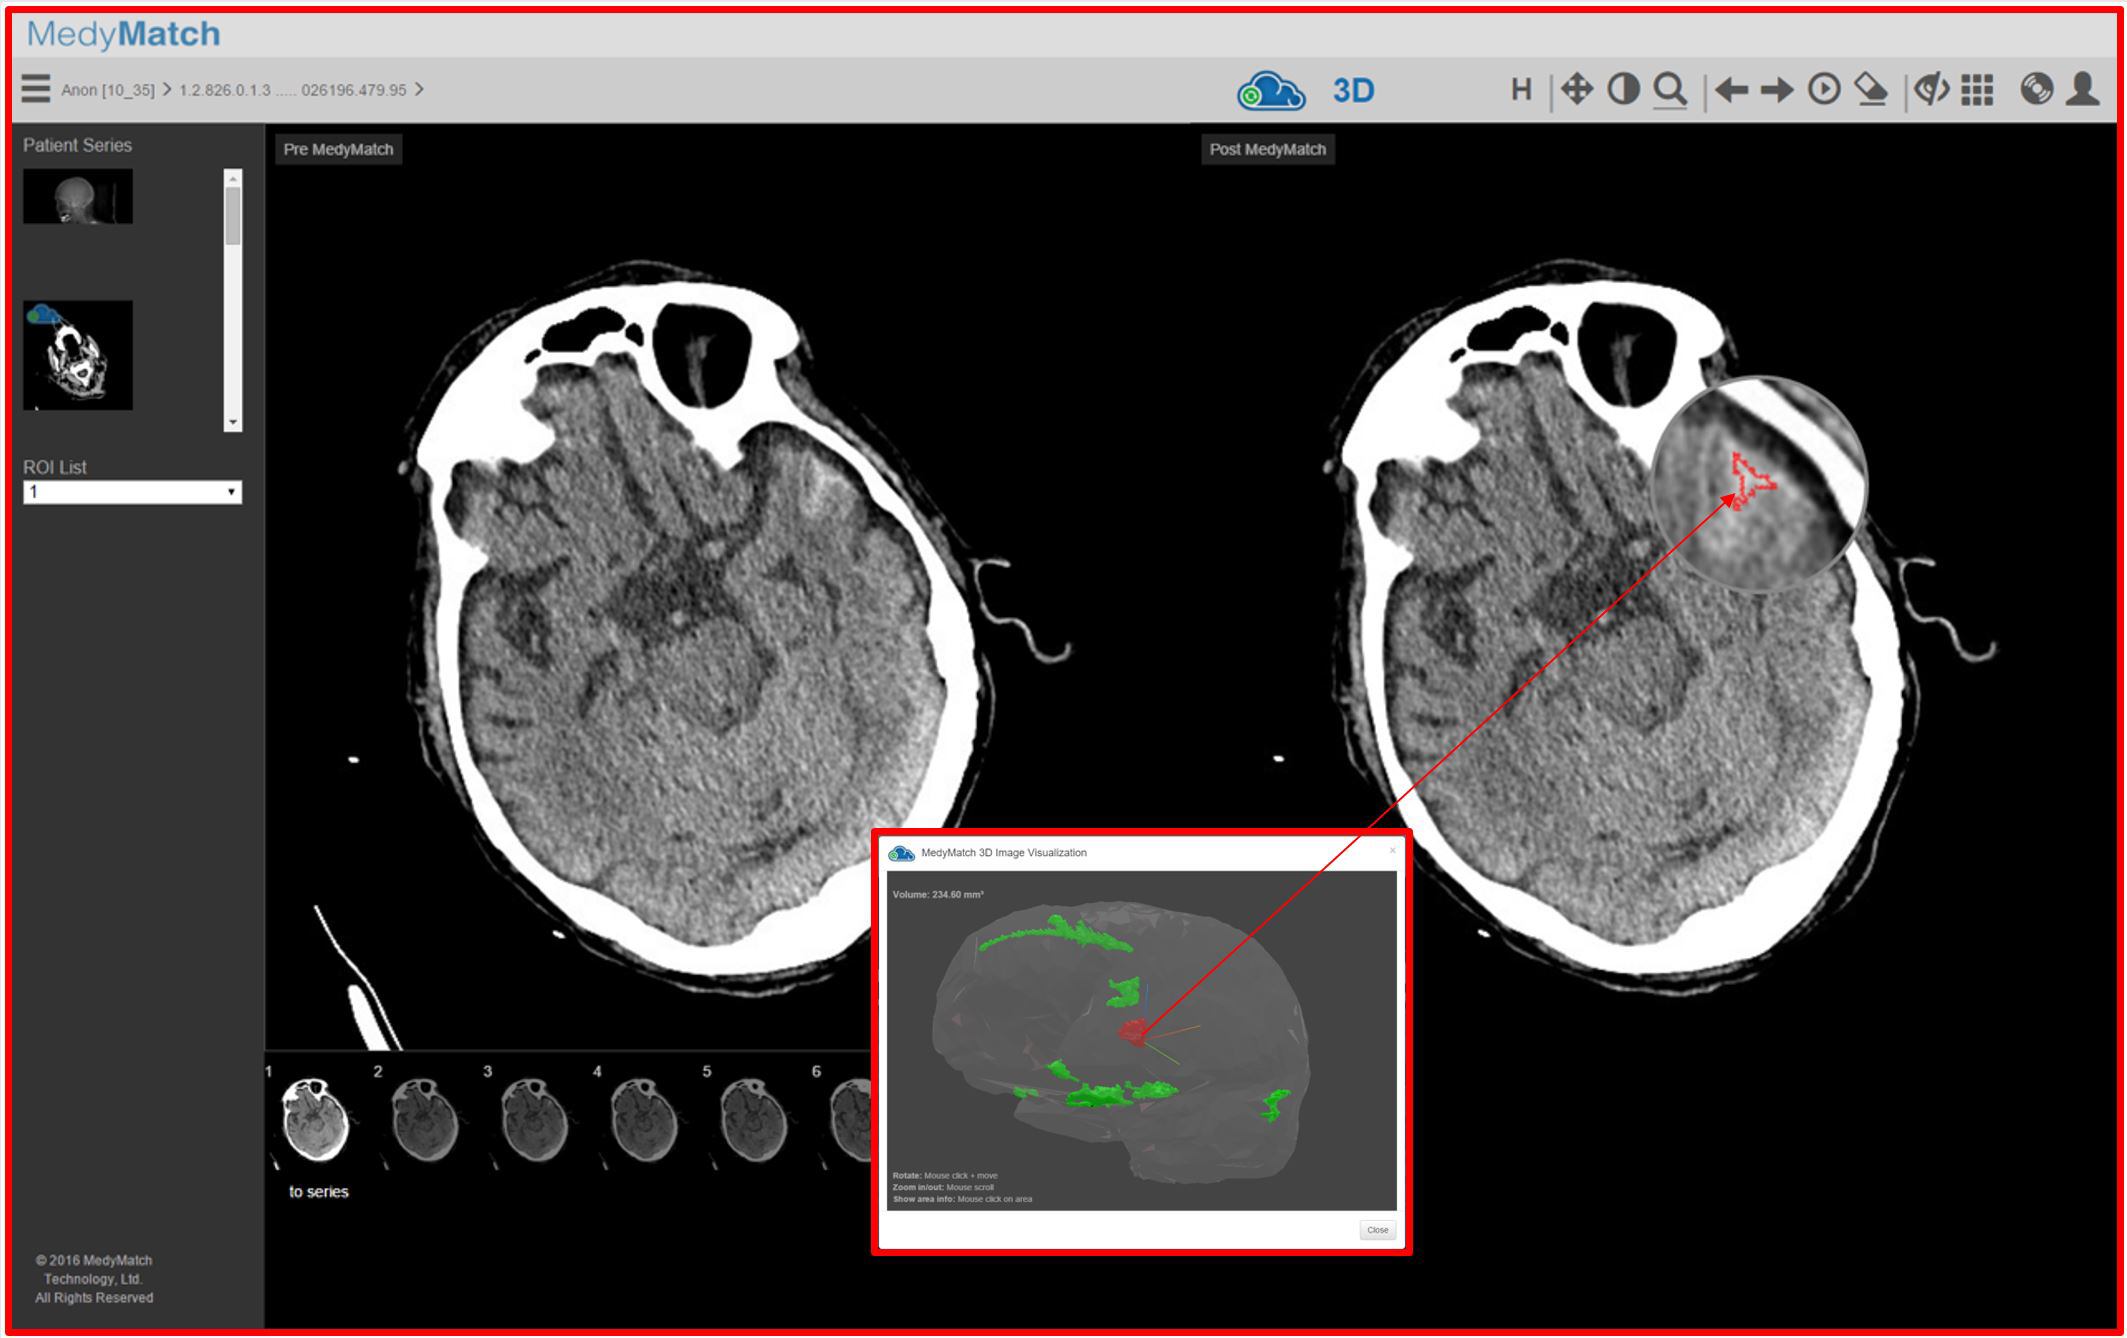

De esta forma los médicos y sus asistentes de las salas de emergencias de los hospitales, por ejemplo, podrán utilizar imágenes de alta resolución que les mostrarán posibles sangrados producidos por traumatismos o accidentes cerebrovasculares.

La solución utiliza un sofisticado algoritmo que combina varias capacidades: el aprendizaje profundo, la visión artificial, los datos de los pacientes y los conocimientos clínicos.

Con todo eso puede brindarle al médico automáticamente imágenes donde se resaltan las regiones del cerebro de interés o donde hay posible presencia de sangrados.